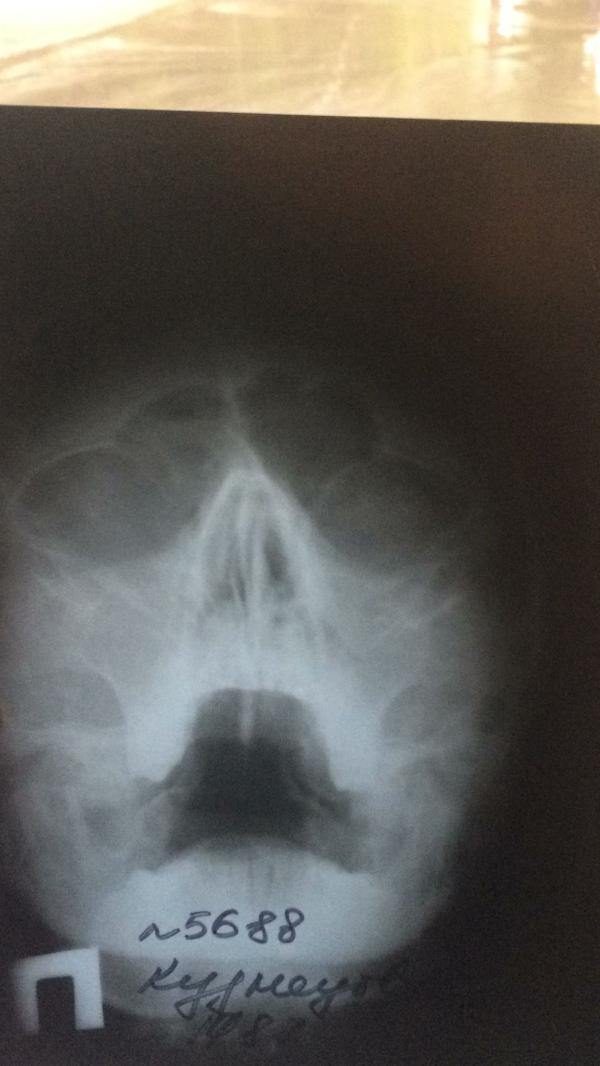

Добрый день я лор врач в декрете )по снимку у вас еще есть фронтит (воспаление лобной пазухи )без антибиотиков не обойтись , рекомендую вильпрофен солютаб 500 1 т 3 р в день ,5-7 дней это аб ,синупрет 1 т 3 р в день ,7 -10 дней для улучшентя оттока гноя из пазух (он на травянной основе ,наблюдайте чтобы у малышки не было аллергической реакцииь,а так он безопасен),в нос спрей сосудосуживающий ринофлуимуцин .Обязательно показаться лору так есть фронтит ,может будет возможность походить на дневной стационар поделать кукушки (промывание пазух под отриц давлением )